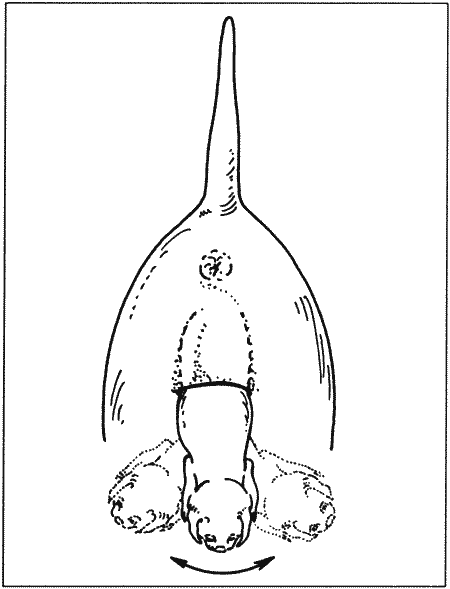

Роды

Снижение концентрации прогестерона перед родами наблюдается у большинства домашних животных и объясняется угнетением у беременной самки надпочечниковой секреции стероидных гормонов, что приводит к выработке эстрогена и простагландина эндометрием. У сук родам предшествует резкое падение концентрации прогестерона с 30 нмоль/л (10 нг/мл) до < 6 нмоль/л (< 2 нг/мл) в плазме крови; это, как сейчас принято считать, играет роль пускового механизма родов. Данный факт подтверждается и тем, что назначение прогестерона вызывает задержку родов, а препараты (например, эпостан), блокирующие его секрецию, — стимуляцию.

Резкое снижение концентрации прогестерона служит индикатором приближения родов. Концентрация > 6 нмоль/л (> 2 нг/мл) свидетельствует о том, что роды не начнутся в ближайшие 14 часов.